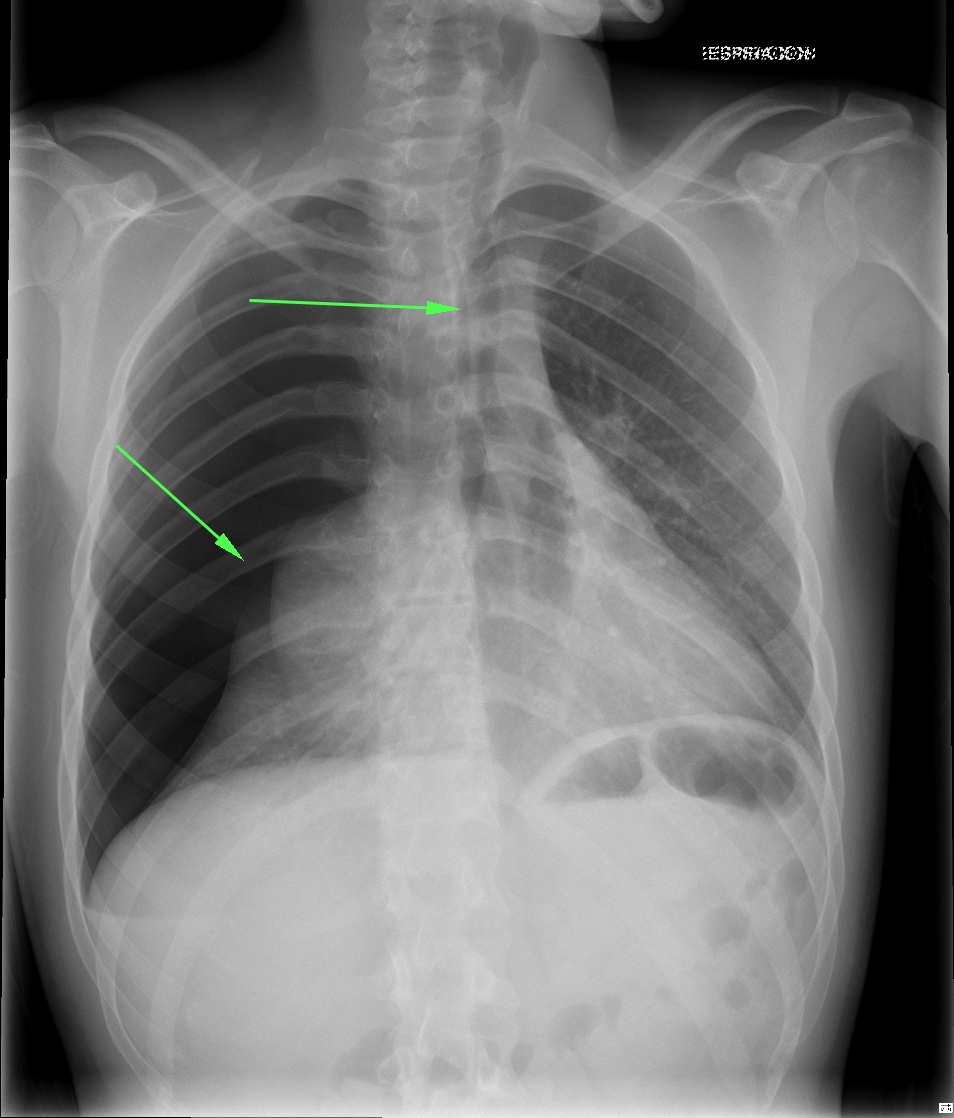

CASO: sospecha de neumonía.

Hallazgos:

- En un principio podríamos decir que existe un aumento de densidad retrocardiaco que podría ser compatible con condensación neumónica a dicho nivel, sin embargo estamos ante una placa poco inspirada, lo cual puede llevarnos a cometer errores diagnósticos.

- Se recomendó volver a realizar la radiografía, observar a continuación:

Ya no se observa el aumento de densidad retrocardiaco, la placa es normal.

INSPIRACIÓN: Una placa bien inspirada es aquella en la que se observar 6-7 arcos costales anteriores o 10-11 arcos costales posteriores. Lo contrario puede producir imágenes falsas de condensaciones o de seudocardiomegalia.